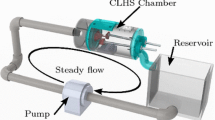

To study the structure and function of each MV, an ex vivo left heart simulation platform was employed. MVs were obtained from fresh, never-frozen ovine hearts sourced from Superior Farms (Dixon, CA). MVs with an anterior leaflet length of 18–20 mm and type I or II papillary muscles (PMs) were selected and excised, preserving the annular and sub-valvular geometry. As shown in Carpentier’s Reconstructive Valve Surgery, these are bulky papillary muscles with either single, or closely clustered PM heads,4 which can be securely mounted to the CLHS. Other PM types have widely spread chordal insertion points, and non-continuous PM structure, and cannot be securely attached and correctly oriented within the CLHS. Using a Ford interlocking suture pattern, the mitral annulus was attached to a plate that separates the atrial and ventricular chambers of a previously validated cylindrical left heart simulator (CLHS)25 (Fig. 1a). Referred to here as an annulus plate, the plate forms a seal between the left atrium and ventricle, only allowing flow to pass through the annular orifice (described further below). Surrounding the annular orifice is a suture cuff onto which the excised valves are sutured. Care was taken to place the sutures just above the natural leaflet hinge line. The papillary muscles were fixed to movable rods that were used to control their position.

(a) The cylindrical left heart simulator (CLHS) features acrylic left atrial (LA) and left ventricular (LV) chambers. An ovine mitral valve (MV) is excised and mounted to the annular plate separating the two compartments. Rods are used to manipulate the positions of the papillary muscles (PMs). (b) The CLHS is inserted into a pulsatile flow loop. A bladder pump is used to drive physiological flows and pressured in the CLHS. Systemic compliance and resistance elements are used to tune the pressure and flow profiles. Pressures and flows are monitored and recorded, along with 3D echo images if the MV.

The CLHS was then mounted in a pulsatile flow loop (Fig. 1b). Powered by a bladder pump, the flow loop replicates pressure and flow curves across the MV (peak trans-mitral pressure of 120 mmHg, cardiac output of 5 L per minute, heart rate of 70 beats per minute), causing it to open and close physiologically. Isotonic saline solution was used as the working fluid in this study, because blood viscosity-matched (water-glycerin) solution is not necessary to match bulk pressure and flow, does not significantly affect the geometry of heart valves, and only affects local variation fluid velocity.21,36 Furthermore, water glycerin solution can impact tissue valve material properties after prolonged exposure.21 Systemic compliance and resistance were adjusted to attain these pressure and flow values. Using echocardiography to clearly visualize the valve coaptation and leaflet shape in real time (iE33 xMATRIX, Philips Healthcare, Andover, MA, USA), PM positions were adjusted to achieve healthy closure (anterior leaflet occupying 2/3 of the A2–P2 diameter, and coaptation length of ~5 mm along the A2–P2 line).25

A vertical, steady flow loop is used to apply glutaraldehyde fixative. After microCT scans in the loaded condition are taken, the cylindrical left heart simulator (CLHS) is mounted vertically into the loop shown here. The leaflets spread and hang normal to the annular plane as glutaraldehyde solution (0.5% in deionized water) fixes the leaflets in place, yielding a repeatable, anatomical diastolic MV geometry.